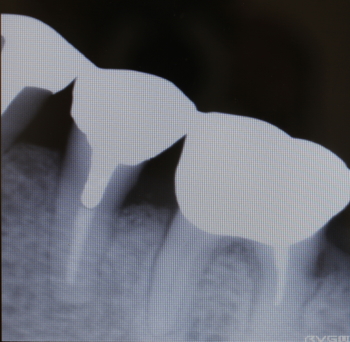

35番遠心より排膿

同部のX-ray